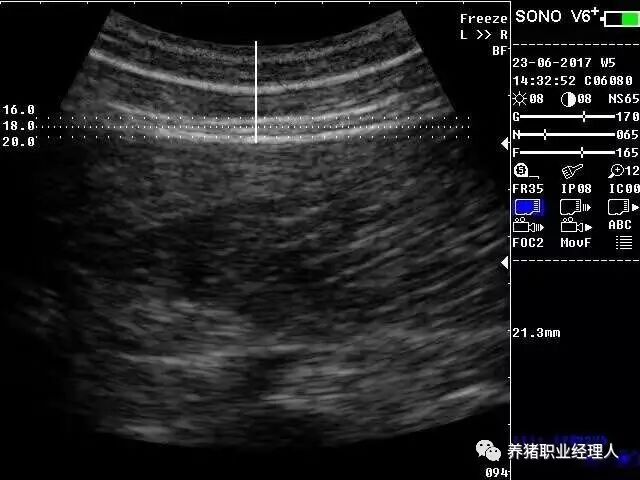

4、背膘仪的显示说明

5、测量读数

打开测定仪开关,把探头轻轻放在P2点上,慢慢转动探头以挤出探头与皮肤之间的空气,读取显示屏上的数字,并进行记录。注意,探头和测量表面必须保持垂直,否则将会导致测量数据错误,左右两侧的P2点都进行测量,取平均值。

检测背膘位置

在使用背膘仪进行测定时,要在测试部位涂上适量的清油,用于使探头与皮肤耦合完好,因为背膘仪探头发出的超声波无法穿透空气,要保证探头与皮肤垂直,同时挤走中间的气泡。